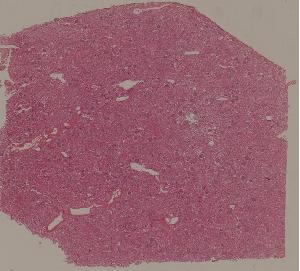

72.膜性肾小球肾炎